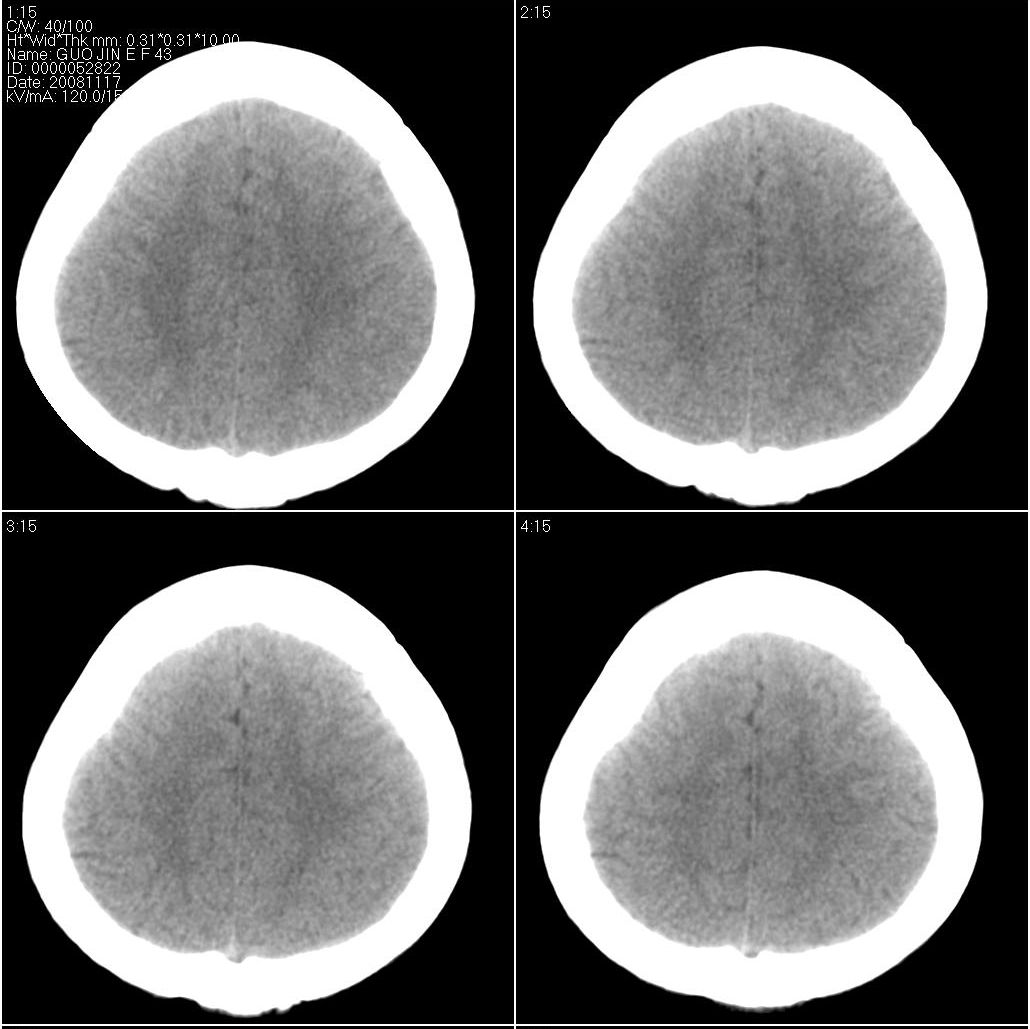

标题: CT16658:女性,49岁。发现右侧额部包块10余年。 [打印本页]

标题: CT16658:女性,49岁。发现右侧额部包块10余年。

支持骨瘤。病史长,病灶与颅骨密度一致,周围软组织没有异常改变。

右额部颅骨外板为主向外突出局限致密骨影,密度均匀,考虑额骨致密骨瘤

右侧额骨致密骨瘤。

考虑右侧额骨致密骨瘤。